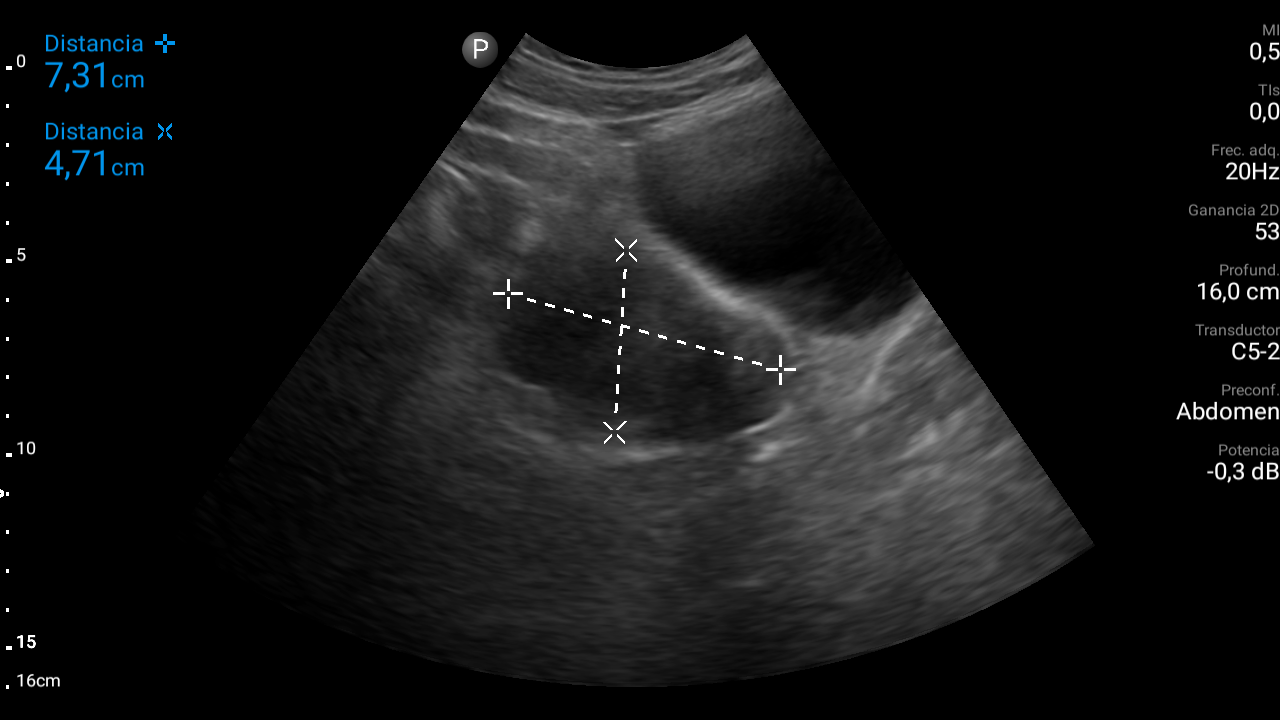

En ecografía abdominal se observa masa hipoecoica dependiente de útero por lo que se remite de forma preferente a ginecología.

En ginecología le realizan ecografía transvaginal, siendo diagnosticada de mioma uterino.